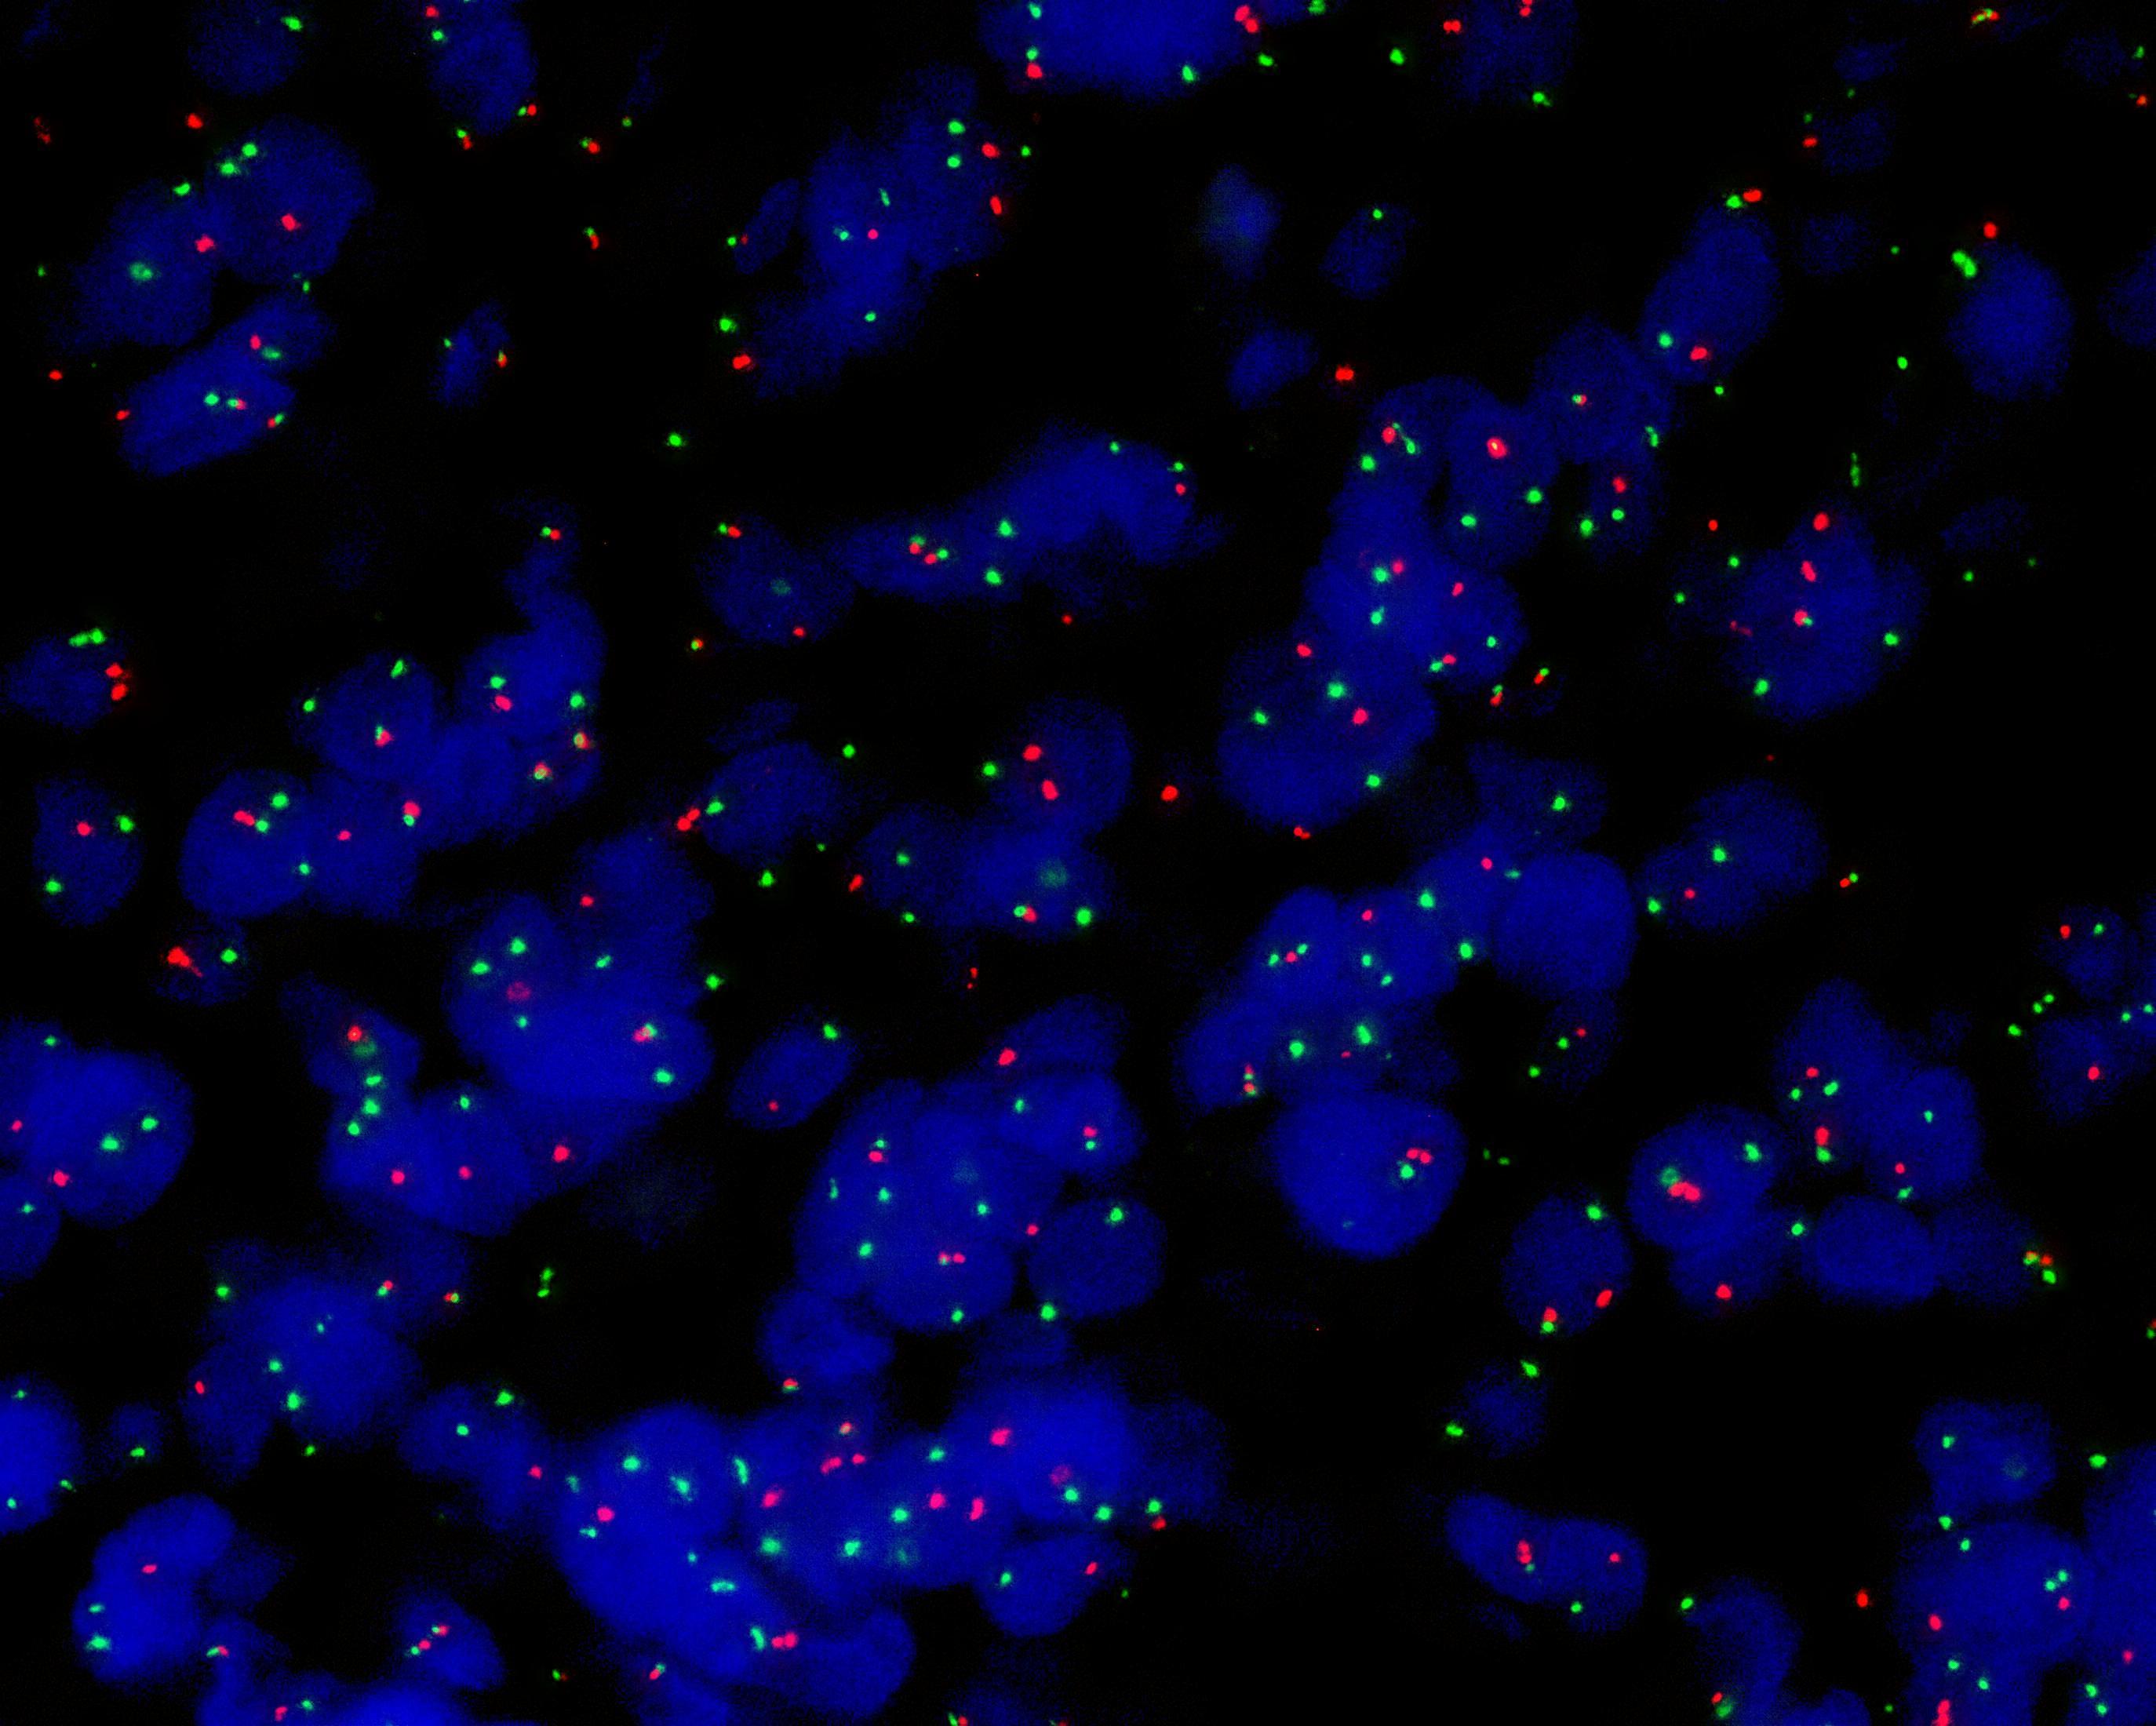

MYC (8q24)/BCL6 (3q27)/BCL2 (18q21) gene break apart probe reagent

MYC (8q24)/BCL6 (3q27)/BCL2 (18q21) gene break apart probe reagent

BCL6 dual color probe

BCL6 gene 5’ end labeled as orange, with a length of 458 kb; BCL6 gene 3’ end labeled as green, with a length of 589 kb.